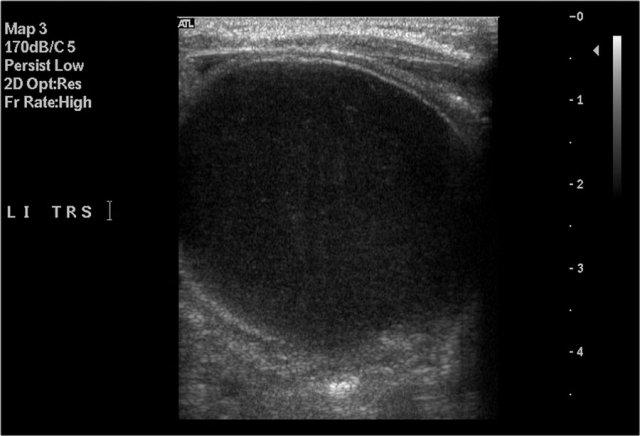

Hình ảnh của một bé trai 1 tháng tuổi được phát hiện MCKD trên siêu âm trước sinh.

Có thể thấy một ít mô thận và nhiều nang lớn.

Trên xạ hình thận với Tc-99-DMSA, không ghi nhận sự hấp thu ở phía bên trái.

Hình ảnh này phù hợp với bệnh thận đa nang loạn sản (MCKD).